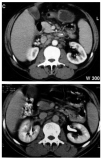

Fig. 1. Tomografía axial computarizada abdominal con múltiples adenopatías retroperitoneales en la imagen de arriba y desaparición de las mismas tras corticoterapia en la de abajo.